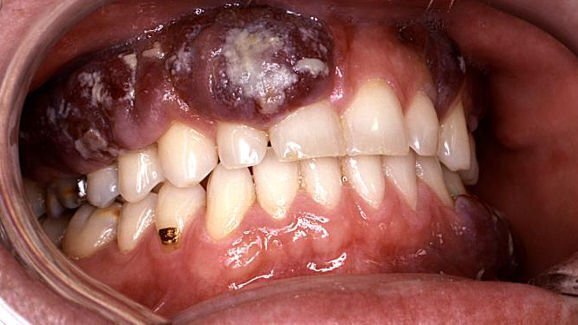

לממצאים עשויים להיות השלכות חשובות עבור חולים עם HIV חיובי ואיידס בפרט , כי כ 20 אחוזים מהחולים ב-HIV מפתחים נגעים מסוג סרקומה של קפוסי ( Kaposi Sarcoma ) בחלל הפה , אשר יכול להתפתח לגידולים ממאירים.

למרות שלא ידוע מה תפקידה של מיקרו סביבה של הפה בהתפתחות גידול KS אוראלי, המחקר הראה כי חומצות שומן קצרות שרשרת מ P. gingivalis ו F nucleatum עשויות לקדם שכפול של וירוס ההרפס הקשורים - ל (KS ) ,אשר הינו הסוכן האטיולוגי הקשור KS , הסביר חוקר ראשי ד"ר Ye Fengchun .

במסגרת המחקר,החוקרים העריכו את בריאות החניכיים של 21 חולים וחקרו דגימות הרוק שלהם. אחד עשרה חולים ( גיל ממוצע של 50 ) אובחנו עם מחלת חניכיים כרונית קשה וkעשרה משתתפים ( גיל ממוצע של 26 ) היו חניכיים בריאים. בסך הכל , החוקרים גילו רמות גבוהות יותר באופן משמעותי של חומצות שומן קצרות שרשרת ברוק של חולים עם מחלת חניכיים חמורה וציינו כי חומצות השומן אפשרו ל KSHV להתרבות.